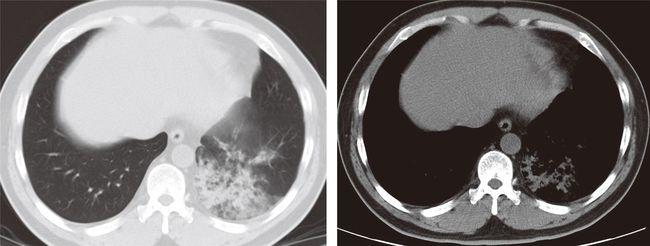

大叶性肺炎ct

大叶性肺炎ct典型图片

大叶性肺炎ct图片讲解

大叶性肺炎的ct图像